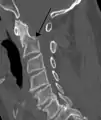

محور (بالإنجليزية: Axis) هي الفقرة العنقية الثانية (C2) من العمود الفقري.[2][3][4] تتصف بوجود النتوء السني على القسم الأمامي للسطح العلوي من جسمها ولهذا النتوء وجيه مفصلي على سطحه الأمامي للتمفصل مع الوجيه الموجود على السطح الخلفي للقوس الأمامي لفقرة الفهقة، حيث يترابط بأربطة تساعد على تثبيت الفقرتين، ان الشدة على الرقبة كالانحناء الحاد للأمام قد يسبب تمزق هذه الأربطة وهكذا تزاح المحور للأمام فتضغط أو تمزق الحبل الشوكي. تتحرك الفقرة الأولى مع الجمجمة على الفقرة الثانية لذا سميت بالمحور، وتمتلك هذه الفقرة جميع صفات الفقرة العنقية النموذجية مع نتوء شوكي قوي تتصل به العضلات التي تحرك الرأس.